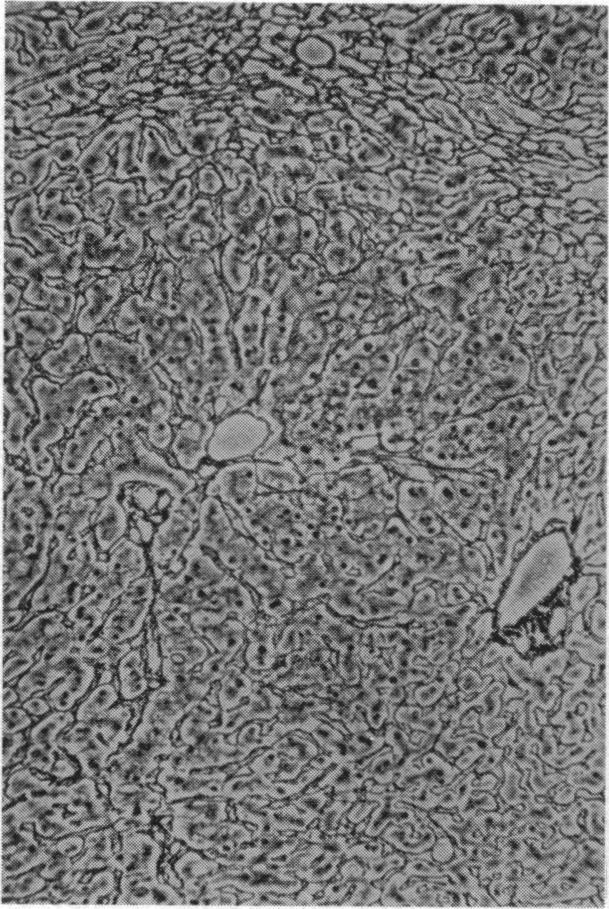

Case of Mesenteric Reticulosarcoma Associated with Gluten-sensitive Steatorrhoea.

Br Med J. 1961 Aug 19;2(5250):496-480.2. doi: 10.1136/bmj.2.5250.496.